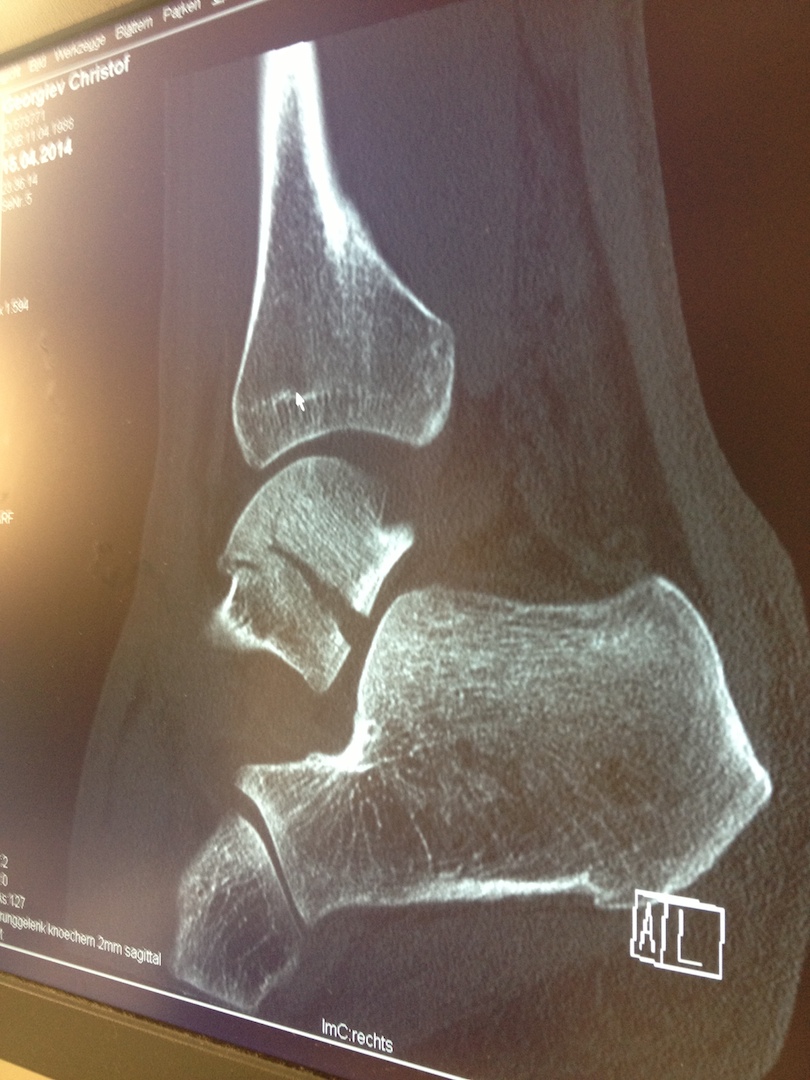

Erstes Bild ist die Seitenaufnahme, dabei sieht man den Riss im mittleren Knochen. Das andere ist das Gelenk von oben, dabei sind die Trümmer zu sehen, die das ganze so langwierig und kompliziert machen...